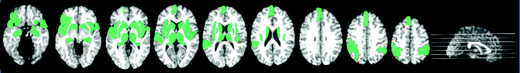

Critical Brain Regions Related with AD Progression.

The top 20 critical brain regions which contributed in AD early detection.